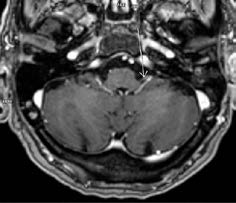

Realiza ressonância magnética crânio encefálica (RM-CE) e de ouvido com injeção de gadolínio, que evidencia realce patológico dos nervos facial, glossofaríngeo e vago esquerdos, de provável natureza inflamatória/infeciosa. Admite-se muito incipiente realce do nervo vestíbulo-coclear esquerdo. Preenchimento da cavidade otomastoideia esquerda, associando-se algum realce dos tecidos moles do ouvido externo esquerdo, de provável natureza inflamatória / infeciosa, cuja ilustração se apresenta nas Figs. 1 e 2.